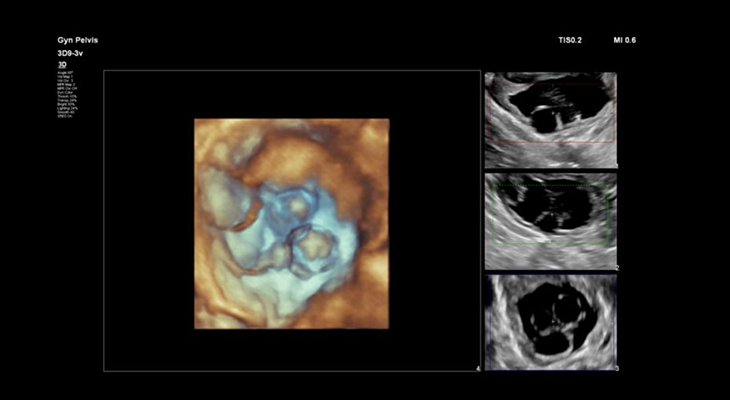

Advanced 3D/4D Sonography scans

Like regular ultrasounds,3D and 4D Sonography use sound waves to create an image of your baby in your womb. What’s different is that 3D ultrasounds create a static three-dimensional image of your baby, while 4D ultrasounds create a live video effect, like a movie — you can watch your baby smile or yawn.